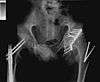

On 25 April 2001 in Garie Beach, Australia, he had a tragic accident in which he was badly injured. His injuries were three broken vertebrae, two broken femurs, a broken collarbone, a punctured lung, and a smashed pelvis. A year after the accident, he returned to the sport. He was always active in BASE jumping.